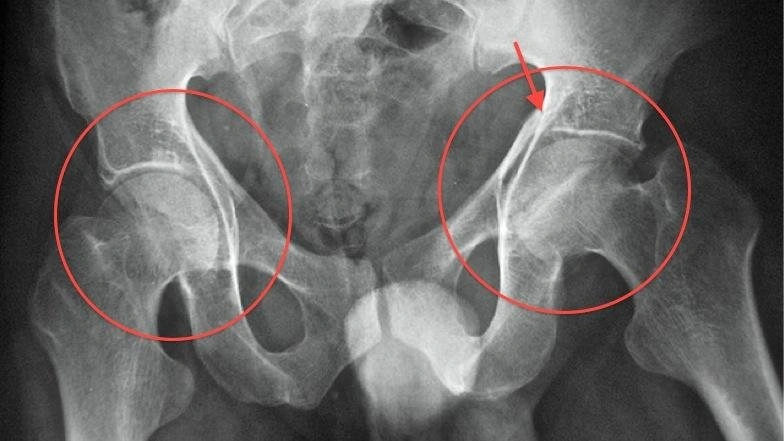

МРТ суставов (плечевого,крестцово-подвздошого, тазобедренного (оба), коленного, голеностопного)

повреждение внутрисуставных и наружных связок, суставных хрящей, повреждения менисков, переломы, разрывы, дегенеративные изменения, остеоартроз, артрит, наличие жидкости в суставе.